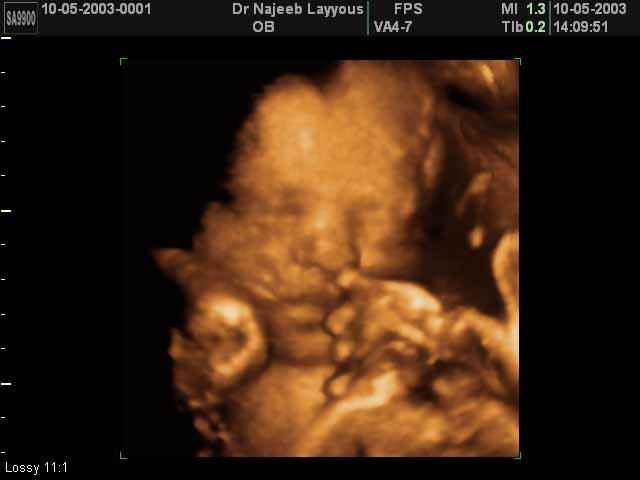

- صور لوجه الجنين في داخل الرحم

- صور لأعضاء الجنين

- تصرفات الجنين داخل الرحم

- أهمية التصوير بالموجات فوق الصوتية رباعي الابعاد في الحمل 4D ultrasound

صور لوجه الجنين بجهاز الالتراساوند ثلاثي الأبعاد | الدكتور نجيب ليوس